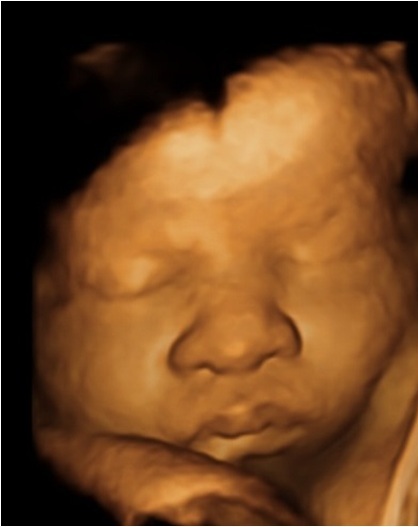

At our Center 3D/4D Ultrasound, you are able to "meet" your unborn baby! We use brand new 3D and 4D ultrasound technology so that you can actually see your baby in live 4D motion while in your womb.

A memorable experience that you will cherish for a lifetime! Nothing compares to seeing 3D and 4D ultrasound images of your unborn baby. With our ultrasound you will be able to see what your baby is going to look like before he or she is born.

Something special happens to parents when the 3D & 4D images are seen compared to the 2D image because the picture of the baby is far more realistic. In the past, expectant parents weren't able to see their baby's face until he or she was born. Moms and dads could only see black and white images of their unborn child through a traditional 2D Ultrasound.